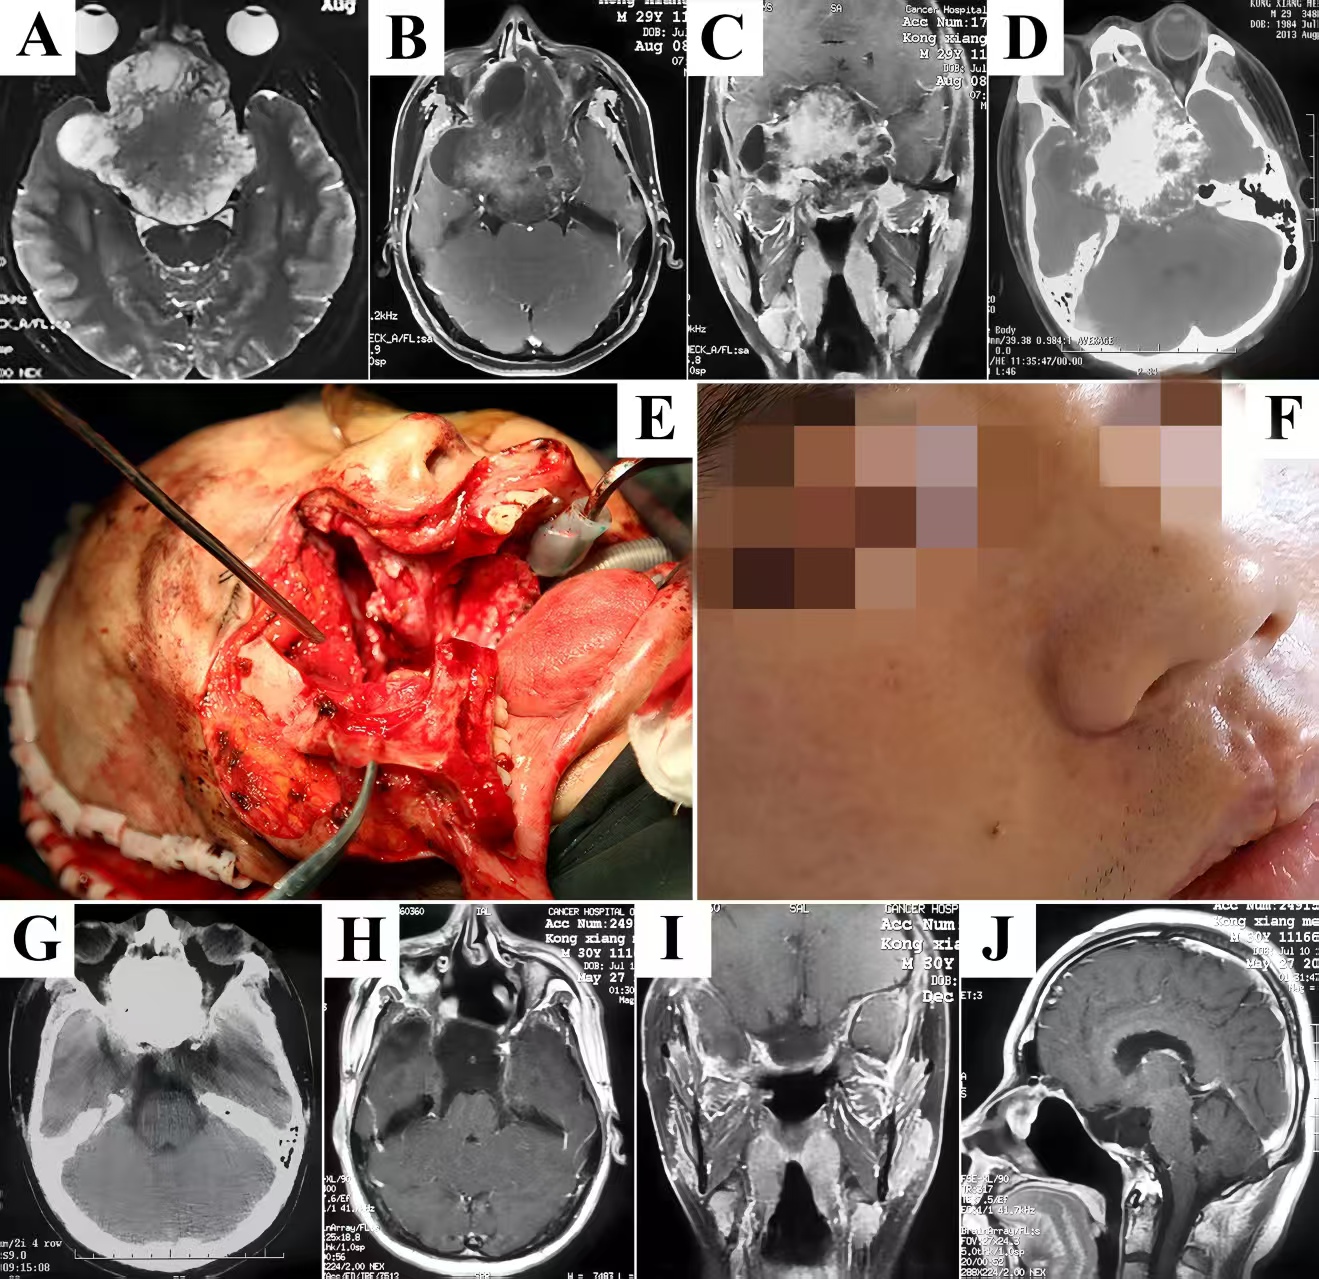

A 49-year-old woman suffered 3-year history of progressive headache, blurring, diplopia, and ptosis. On neurological examination, vision loss, partial cranial nerve (CN) III palsy, and complete CN VI palsy of the right eye were observed. T1-weighted post-gadolinium MRI revealed significantly homogeneous contrast enhancement of a lesion which involved the sellar, CS, clivus, parasellar area, and petroclival region (Fig. 3A-C). The endoscopic endonasal technique or extradural subtemporal transpetrosal access (Kawase’s approach) was not recommended because severe bleeding due to tumor debulking and dissection across the cranial nerves might pose great risks to the patient. Standard maxillary swing procedure was carried out. After identifying superoposterior displacement of the cranial nerves, the tumor was peeled off along its capsule as a whole under an almost bloodless view (Fig. 3D). There was no surgical complication, and the tissue diagnosis was schwannoma. The patient was relieved of visual defects and extraocular movements limitation at follow-up, and MRI scans demonstrated no evidence of tumor growth (Fig. 3E&F).

Figure 3. A hypervascularized schwannoma migrating across the midline to the contralateral side was totally resected as a whole. Vivid contrast enhancement was shown in T1-weighted MRI in axial (A), coronal (B), and sagittal (C) planes. The lesion was peeled off along its capsule surface in a single piece under an almost bloodless view. Histopathological examination of excised specimen (D) determined the diagnosis of schwannoma, and postoperative T2-weighted MRI in axial (E) and sagittal (F) planes demonstrated an absence of tumor. MRI, magnetic resonance imaging.